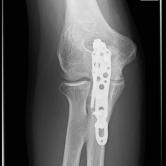

Röntgenbilder